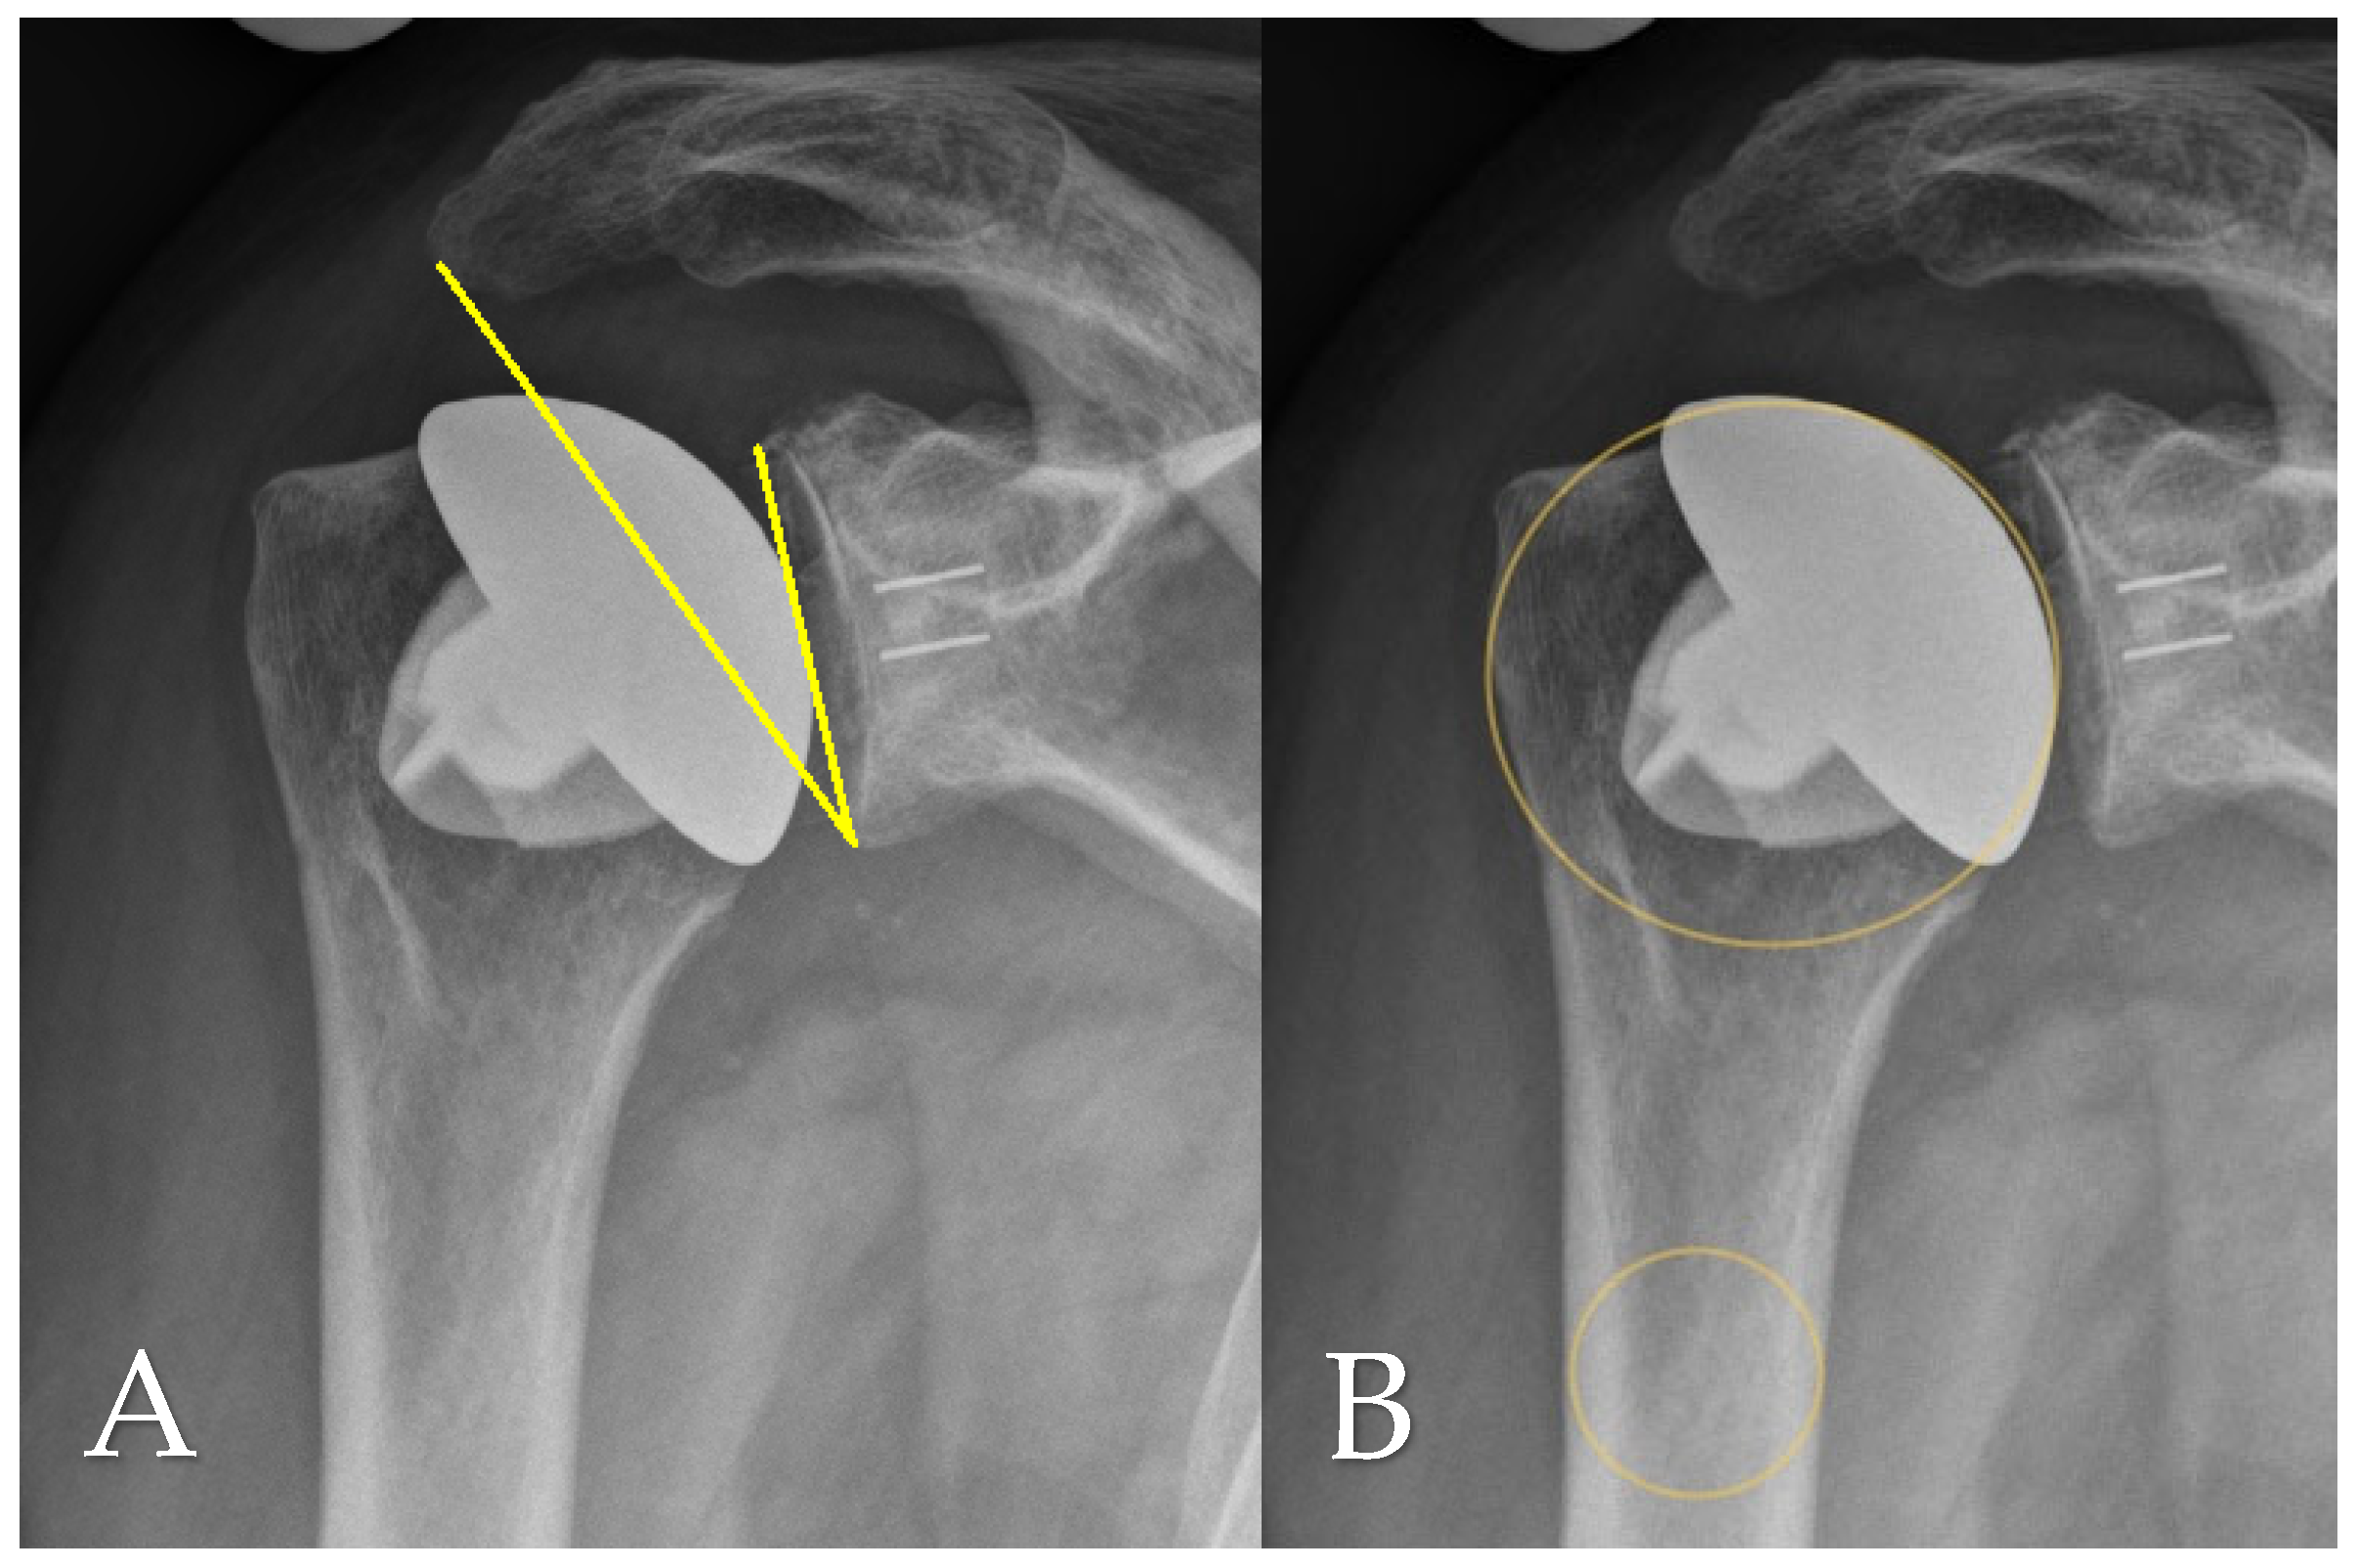

In the present study, only radiolucent lines >2 mm at the cement–bone interface of the glenoid component were defined as gRLL and included in the analysis, in accordance with established radiographic thresholds [6]. Thin radiolucent lines ≤2 mm without evidence of component migration are frequently observed in clinical practice but were not classified as gRLL in this study. These minor changes have been shown to persist over time without leading to clinical symptoms or implant loosening [3]. For standardized localization, gRLL at the cement–bone interface of the glenoid component were classified according to the system by Streck et al. [6]. This divides the glenoid face into three anatomical thirds (superior, medial, inferior) based on the visible distribution of gRLL on standard AP radiographs (Figure 3). The extent of gRLL was quantified by counting the number of affected zones. Patients were subsequently classified according to the extent of gRLL, with extensive gRLL defined as involvement of 3 zones. GSC was defined as migration of the glenoid component within the bone relative to its initial postoperative position. This was determined through comparative analysis of standardized true AP radiographs taken immediately postoperatively and at the final follow-up (Figure 4).

Figure 3. Representative AP view showing radiolucent zones at the cement–bone interface of the glenoid component. Based on the method by Streck et al. [6], the glenoid face was divided into three anatomical thirds: superior (yellow), medial (orange), and inferior (green).